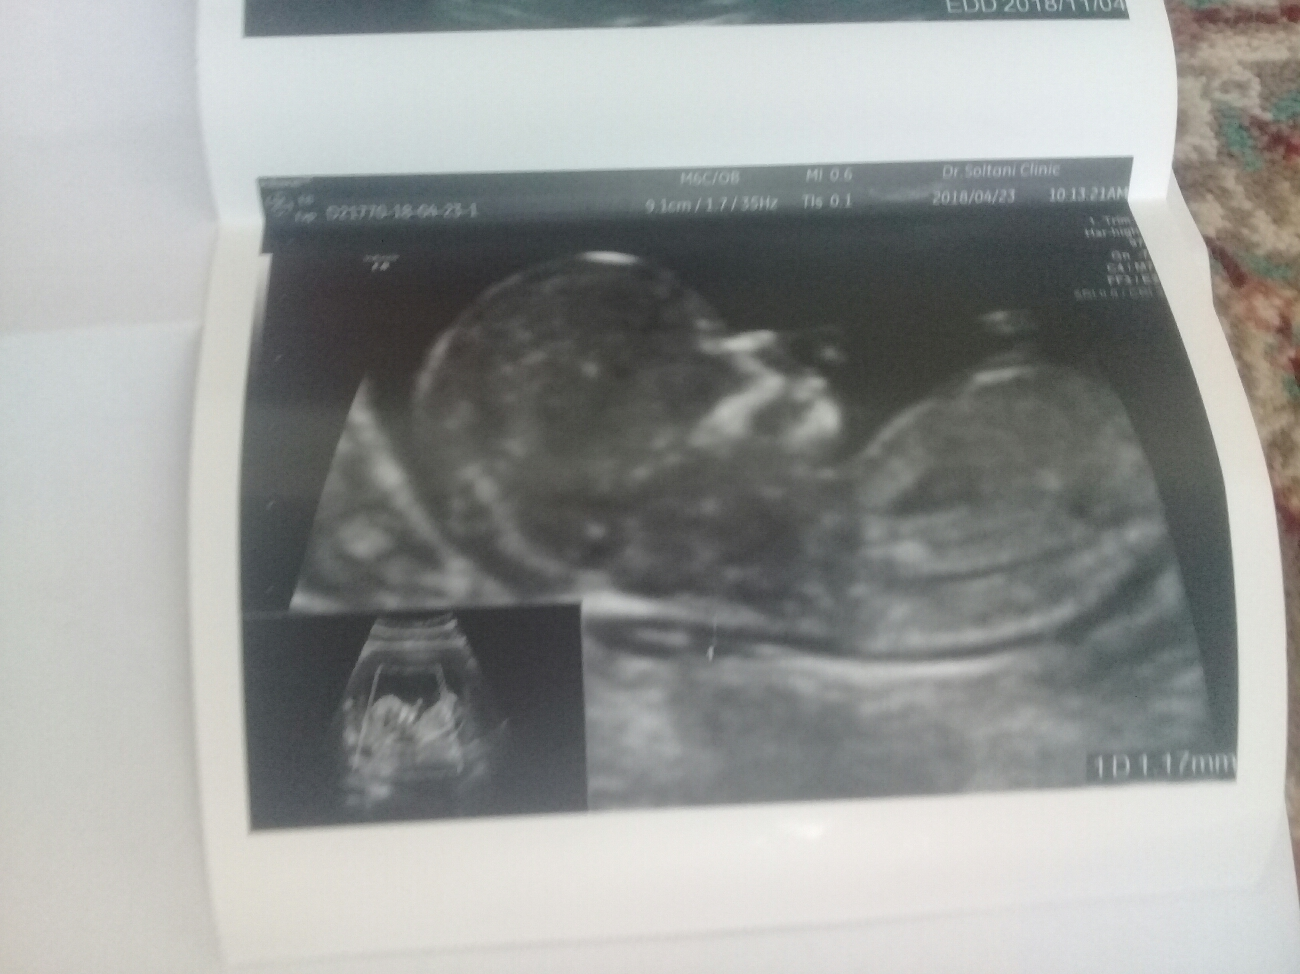

سلام پزشک اوما وقتتون بخیر. میشه لطف کنید سونو غربالگری منو شرح بدین.ممنون از لطفتتون

سلام همه موارد نرمال است